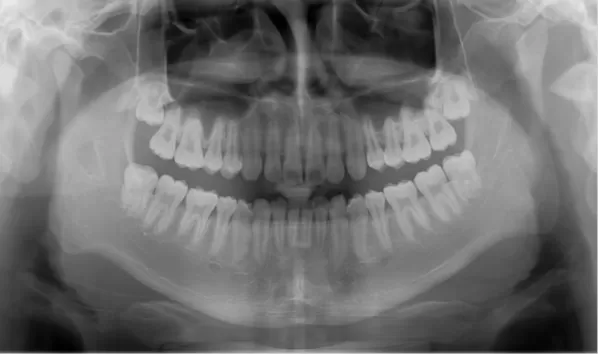

X-rays before treatment

[Panoramic Radiography/Lateral Cephalogram]